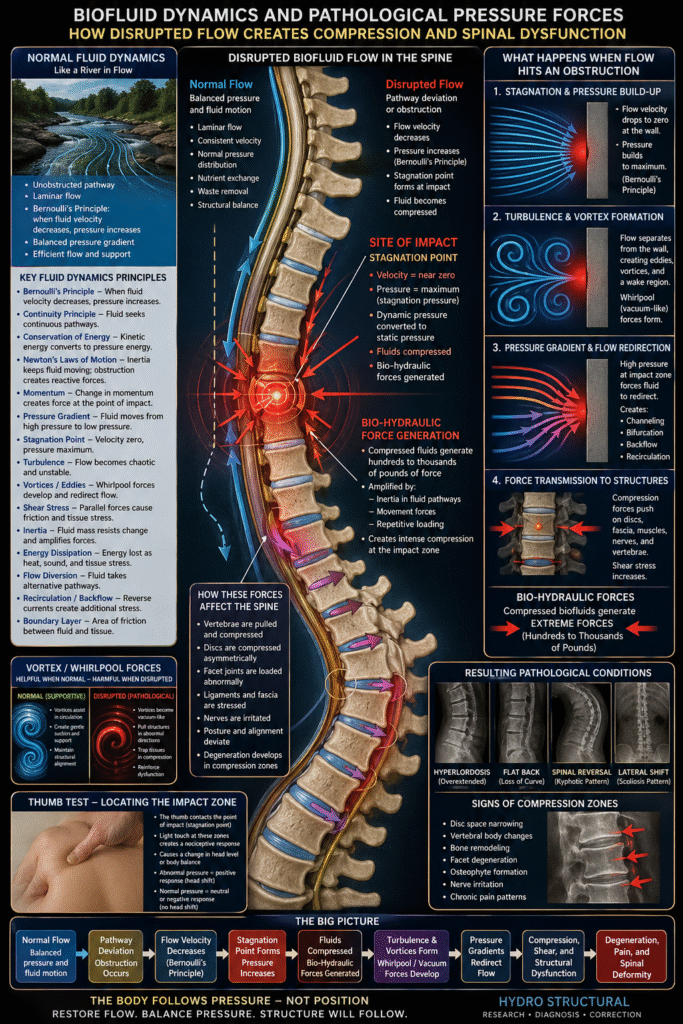

Pathological Pressure in the Body: A Fluid Dynamics Perspective

When biofluid pathways in the body deviate from their normal routes, the system begins to behave like a river encountering an obstruction. What should be smooth, continuous flow along organized streamlines becomes disrupted. Instead of balanced, near-laminar flow, the body develops turbulence, pressure buildup, and chaotic redistribution.

At its core, this is governed by Fluid Dynamics.

From Smooth Flow to Disruption

In a healthy system:

Flow velocity is consistent

Volumetric and mass flow rates are balanced

Dynamic pressure and static pressure remain in equilibrium

But when a pathway is restricted or deviated:

Momentum of moving fluid is interrupted

Kinetic energy converts into pressure energy

A localized obstruction forms within the system

This creates the biological equivalent of a barrier in a flowing river.

The Point of Impact: Stagnation, Compression, and Bio-Hydraulic Force

At the site of obstruction, fluid motion abruptly slows, forming a stagnation point:

Flow velocity drops toward zero

Pressure rises to its maximum (stagnation pressure)

Dynamic pressure converts into static pressure

This behavior is explained by Bernoulli’s Principle, which states that when fluid velocity decreases, pressure increases.

At this point of impact, fluids do not simply stop—they become compressed. This compression begins to generate what can be described as bio-hydraulic forces.

Hydro Structural research has demonstrated that these forces are not trivial. When fluid is confined and compressed within tissue compartments, it can generate hundreds to even thousands of pounds of force. These forces are further amplified by:

Inertia within the fluid pathways

Ongoing body movement

Repeated loading cycles

What begins as a flow disruption becomes a force-amplifying system.

In Hydro Structural diagnostics, this is precisely where the thumb test identifies dysfunction. The thumb locates the point of impact, where:

Pressure has accumulated

Flow has been disrupted

Bio-hydraulic forces are concentrated

This point reflects a localized pressure gradient where fluid is no longer moving efficiently from high-pressure to low-pressure zones.

Turbulence, Vortices, Compression and “Vacuum Whirlpool” Forces

Once the flow is disrupted, the system transitions into Turbulence:

Eddies and vortices begin to form

Vortex shedding creates oscillating forces

A wake region develops beyond the obstruction

In biological systems, these vortices can behave like whirlpools creating vacuum-like forces.

Under normal conditions, fluid dynamics can help support structure. But when disrupted, these vortex-like forces can reverse their role:

Instead of stabilizing, they begin pulling tissues in abnormal directions

They create vacuum-like forces within the system

They draw structures into zones of compression

These forces can effectively trap and hold tissues in pathological positions, reinforcing misalignment through pressure—not structure.

Pressure Gradients and Force Redirection

As pressure builds at the stagnation point:

Strong pressure gradients develop (high → low pressure)

Fluids are forced to redirect

Flow diversion, channeling, and bifurcation occur

Backflow and recirculation zones emerge

These compensations spread dysfunction throughout the system, creating:

Secondary zones of underpressure

Additional regions of compression and expansion forces

A cascade of imbalance, normal fliud tensegrity is losed.

Compression Zones and Degeneration

The areas where these forces concentrate become compression zones.

These zones are not theoretical—they are visible:

They correspond to areas of tissue degeneration

They align with regions of disc compression

They show structural changes in vertebrae over time

Using Hydro Structural radiographic analysis, these pathological forces can be:

Identified

Mapped

Understood in terms of direction and magnitude

This allows practitioners to see:

Where pressure is impacting the system

How forces are deviating from their normal pathways

Which direction those forces are driving compression